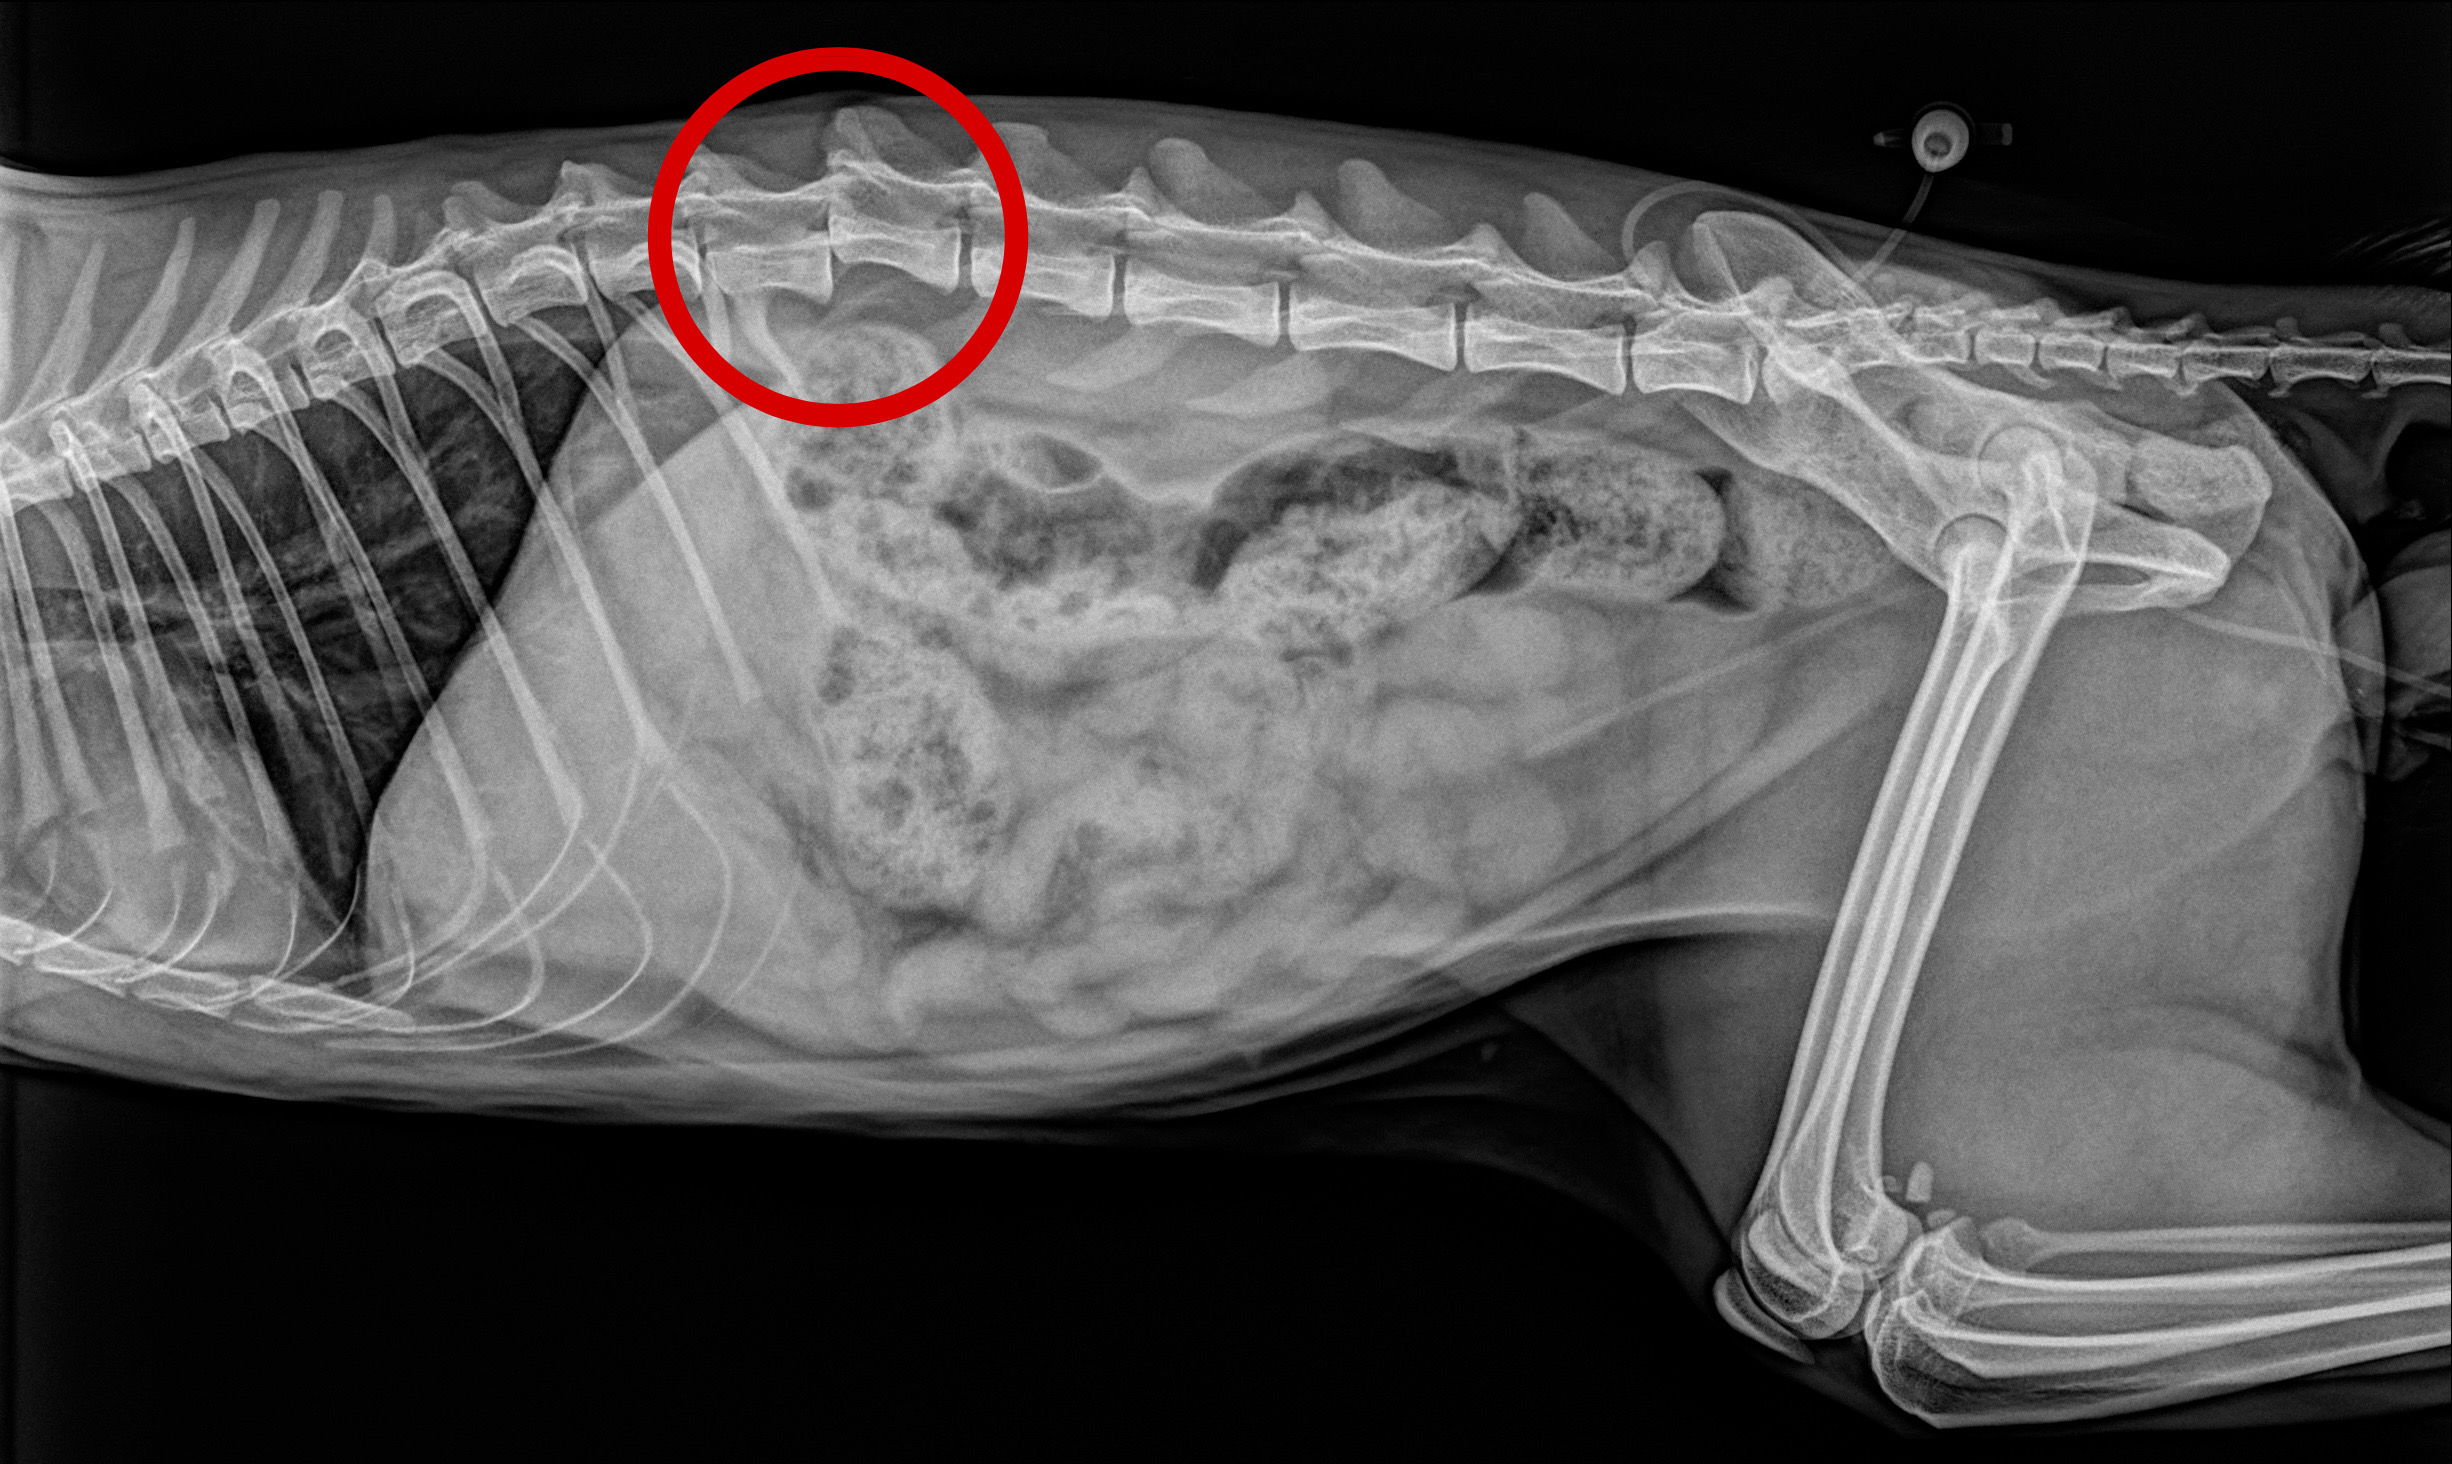

<手術前レントゲン>

第13胸椎-第1腰椎において椎体が脱臼しています。